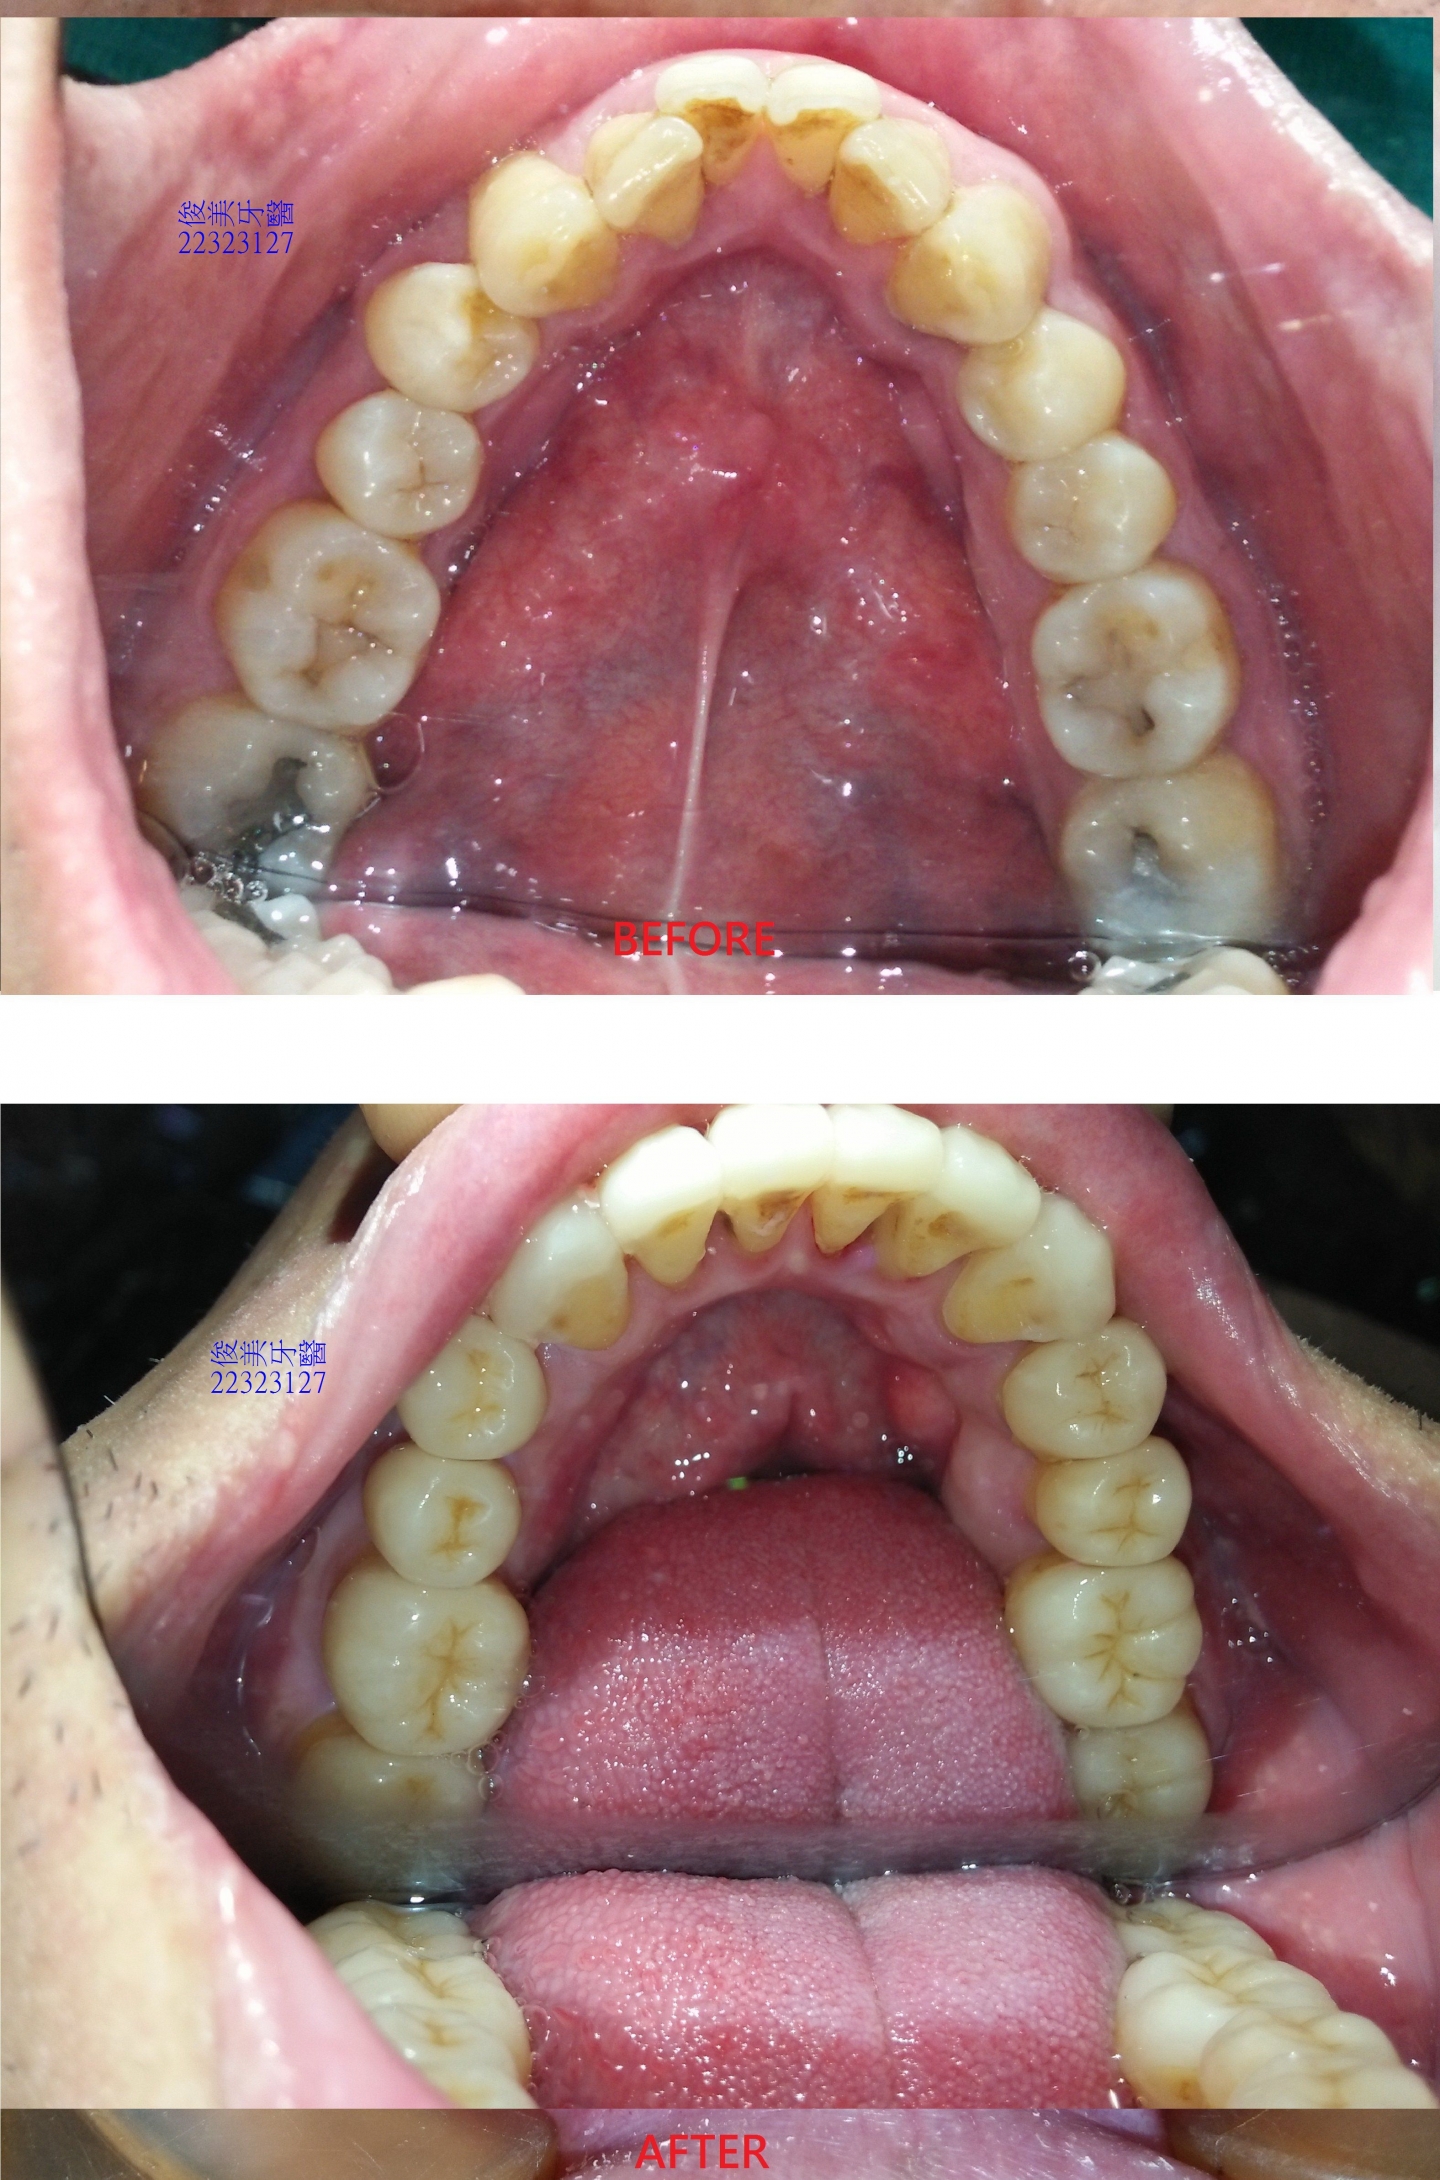

上顎原始狀況。

下顎原始狀況。牙齒開始內傾到舌側位置。

上顎治療後狀況。

下顎治療後狀況。

治療前、後牙弓形狀差異比較。